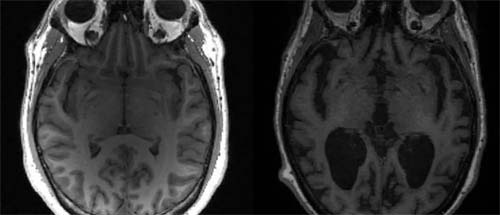

Os cientistas trabalharam com roedores e com amostras cerebrais post mortem de bancos de encéfalos da Universidade de São Paulo (USP) e de uma instituição da Holanda. Ao todo, foram analisadas 16 amostras de pessoas de meia-idade e 14 de idosos. Os pesquisadores investigaram transformações nos astrócitos, células nervosas que dão sustentação e ajudam a controlar o funcionamento dos neurônios.

O estudo mostrou que a quantidade de lamina-B1 diminui com o envelhecimento. A identificação das alterações na lamina-B1 pode ajudar os cientistas a distinguir o que é um sinal normal do envelhecimento das alterações associadas a distúrbios cognitivos.